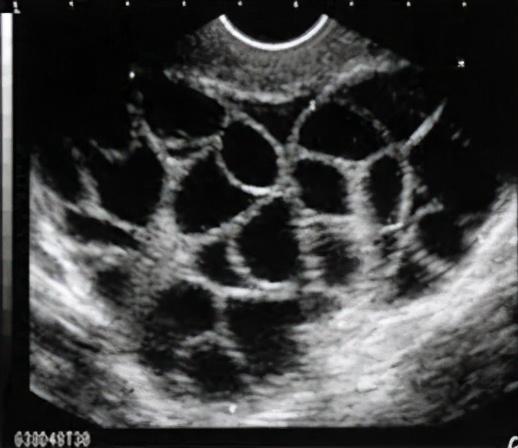

1. 对“卵妹”的伤害